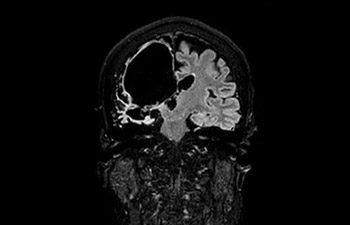

Cerebro

Lesión cerebral

con Compressed SENSE